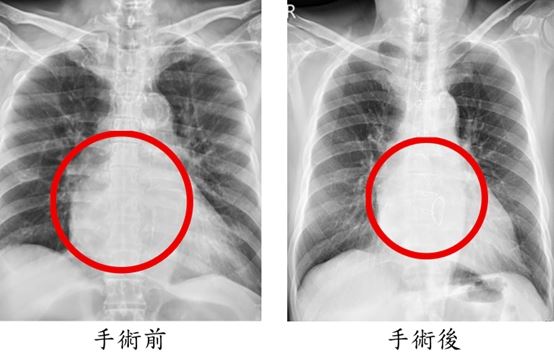

手術歷時8小時,醫師依序完成冠狀動脈繞道手術、僧帽瓣修補、心室重建與冷凍去顫治療。術後隔天患者即順利移除呼吸器,再觀察一天後轉出加護病房,接受心臟復健後平安出院。術後一個月追蹤顯示,心臟收縮功能由原本32%提升至53%,瓣膜逆流消失,24小時心電圖也未再出現心室性心律不整。陳姓老翁不僅恢復日常生活,身體狀況甚至比手術前更好。